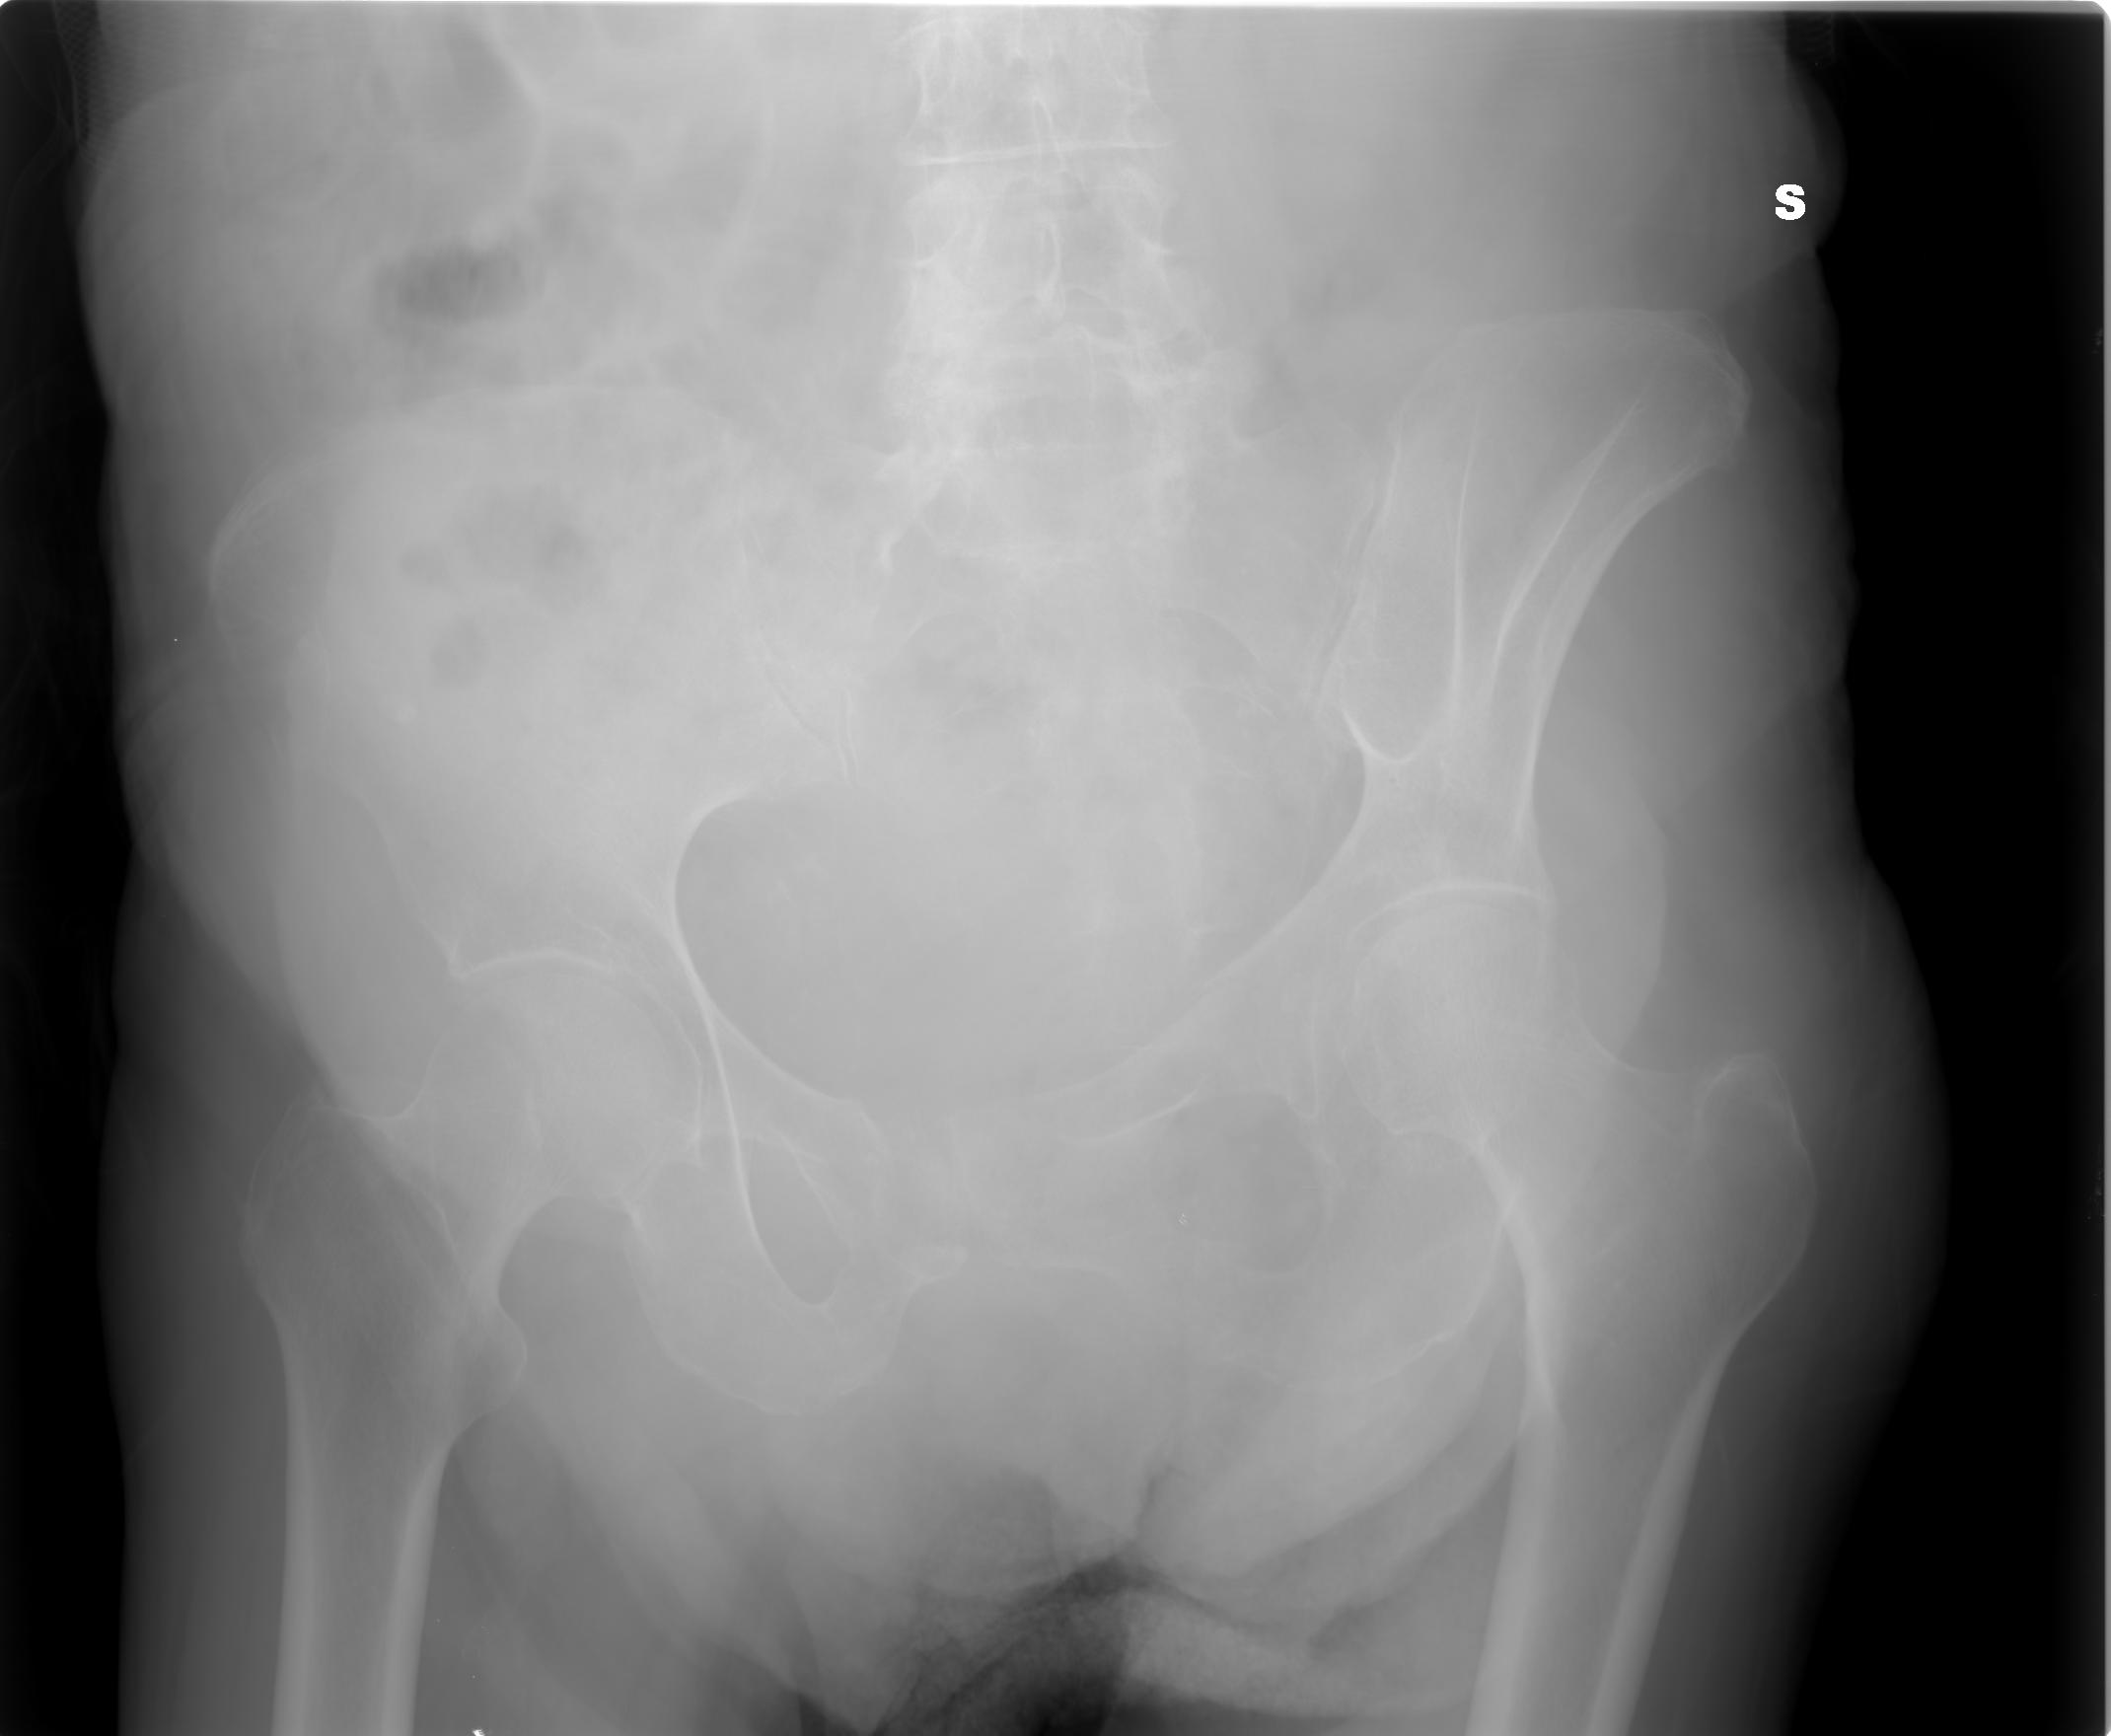

SALVE, ho ritirato un referto lastra per mia madre 80 anni e dice le seguenti parole: per quanto apprezzabile nel radiogramma a disposizione si osserva frattura composta della branca ile pubica sinistra .Sospetta frattura (o esiti fratturativi?) a carico dell branca ischio pubica omolaterale.

allego le lastre potete consigliarmi?

I00001 (1).JPG

[ 122.11 KiB | Osservato 1195 volte ]